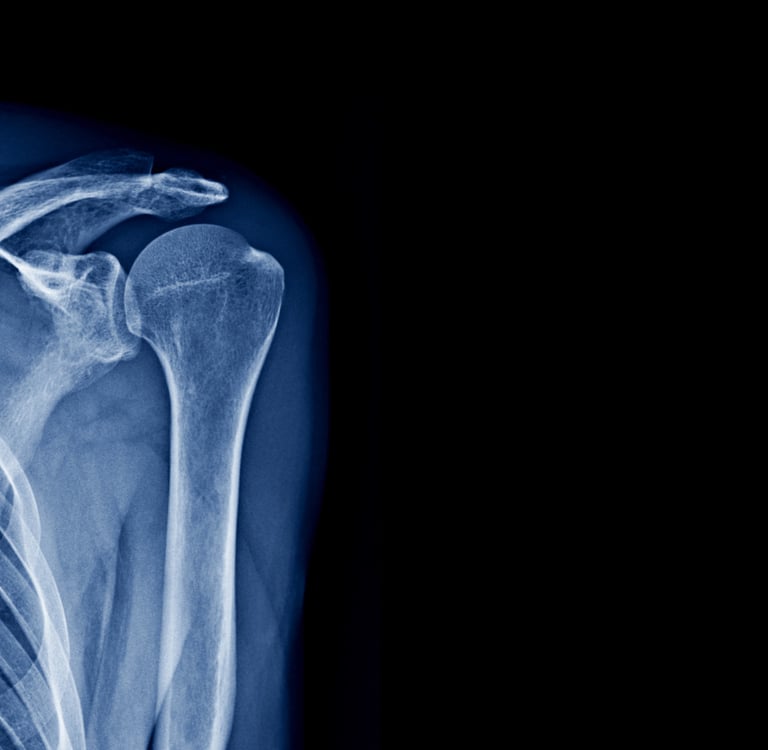

Η αρθροπλαστική ώμου είναι μία χειρουργική επέμβαση που στοχεύει στην αντικατάσταση της φθαρμένης ή κατεστραμμένης άρθρωσης του ώμου με μια τεχνητή πρόθεση (ενδοπρόθεση). Η εν λόγω επέμβαση συνήθως ενδείκνυται για ασθενείς που πάσχουν από σοβαρή αρθρίτιδα του ώμου, τραυματισμούς ή άλλες φλεγμονώδεις παθήσεις που έχουν προκαλέσει πόνο, περιορισμένη κινητικότητα και δυσκολία στις καθημερινές δραστηριότητες. Η αρθροπλαστική ώμου έχει αποδειχθεί ιδιαίτερα αποτελεσματική στην αποκατάσταση της λειτουργικότητας του ώμου και στην ανακούφιση του πόνου, βελτιώνοντας την ποιότητα ζωής των ασθενών.

Η ανάγκη για αρθροπλαστική ώμου προκύπτει κυρίως σε περιπτώσεις οστεοαρθρίτιδας του ώμου ή σοβαρών τραυματισμών, όπως οι ρήξεις του στροφικού πετάλου που δεν ανταποκρίνονται σε συντηρητική θεραπεία. Εάν ο πόνος γίνεται χρόνιος και οι ασθενείς δεν μπορούν να εκτελούν τις καθημερινές τους δραστηριότητες (όπως το να σηκώσουν το χέρι ή να σηκώσουν βάρη), η αρθροπλαστική είναι μια ιδανική λύση. Η ένδειξη της αρθροπλαστικής βασίζεται στη σοβαρότητα των συμπτωμάτων και στην ανικανότητα του ασθενούς να ανταποκριθεί σε άλλες θεραπείες.

Η αρθροπλαστική ώμου περιλαμβάνει την αφαίρεση των φθαρμένων ή κατεστραμμένων οστών και χόνδρων του ώμου και την αντικατάστασή τους με τεχνητή πρόθεση. Η επέμβαση μπορεί να γίνει με διαφορετικές τεχνικές, ανάλογα με την κατάσταση του ασθενούς και την αιτία της βλάβης, όπως η πλήρης ή η μερική αντικατάσταση της άρθρωσης. Ο ορθοπεδικός χειρουργός εξετάζει κάθε περίπτωση και επιλέγει την κατάλληλη τεχνική για την αποκατάσταση της φυσιολογικής κινητικότητας και της λειτουργικότητας του ώμου.